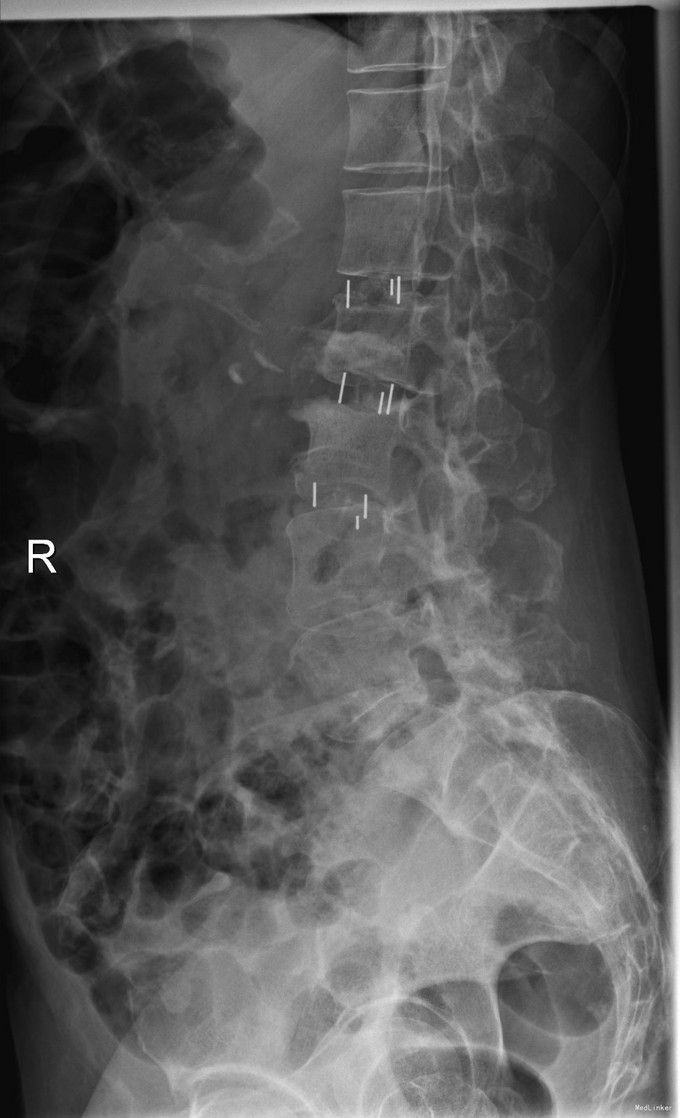

主诉:右下肢麻木11年,腰部酸痛无力 现病史:女性患者,65岁,患者于11年前无明显诱因下出现右下肢麻木,自大腿至右踝部,站立位加重。未予重视,后期出现腰臀部僵硬,弓背僵硬无力,自主行走距离不足200米,曾于06年经X线平片及MRI检查:腰椎椎管狭窄伴有腰椎滑脱,椎间盘突出等。

查体:侧弯畸形,右臀部及右下肢麻木疼痛,腰部活动受限,难以站立。右侧支腿抬高试验60°。双下肢肌力肌张力可。 辅助检查:平片:腰椎侧弯,椎体滑脱,曲度后凸 磁共振:L2-3,L4-5,L5-S1腰椎椎管狭窄,l2-3L3-4L4-5L5-S1腰椎间盘突出,腰椎退变

诊断: 腰椎侧弯,腰椎间盘突出 治疗:1期微创侧路椎体融合术+2期 微创后路经皮内固定术